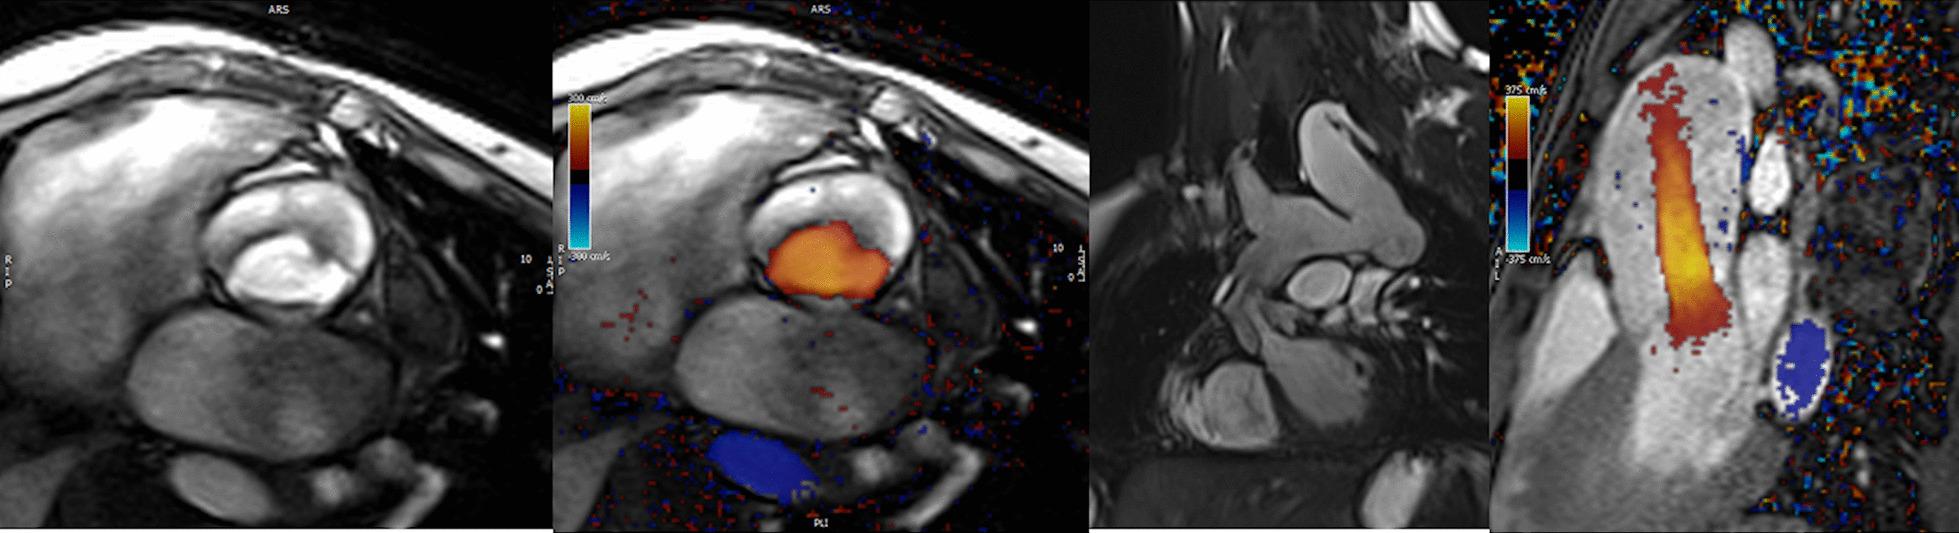

Cardiovascular magnetic resonance (CMR) has been utilized in the management and care of pediatric patients for nearly 40 years. It has evolved to become an invaluable tool in the assessment of the littlest of hearts for diagnosis, pre-interventional management and follow-up care. Although mentioned in a number of consensus and guidelines documents, an up-to-date, large, stand-alone guidance work for the use of CMR in pediatric congenital 36 and acquired 35 heart disease endorsed by numerous Societies involved in the care of these children is lacking. This guidelines document outlines the use of CMR in this patient population for a significant number of heart lesions in this age group and although admittedly, is not an exhaustive treatment, it does deal with an expansive list of many common clinical issues encountered in daily practice.

心血管磁共振(CMR)在儿科患者的管理和护理中已经应用了近 40 年。它已经发展成为评估最小的心脏的宝贵工具,用于诊断、介入前管理和随访。尽管在许多共识和指南文件中提到,但在儿科先天性心脏病和后天性心脏病领域,目前还缺乏一份由众多参与儿童护理的学会共同认可的、最新的、独立的、针对 CMR 使用的大型指南。本指南文件概述了 CMR 在该年龄段的许多心脏病变中的应用,尽管不能说是详尽的治疗方法,但它确实涉及了在日常实践中经常遇到的许多常见临床问题的广泛列表。